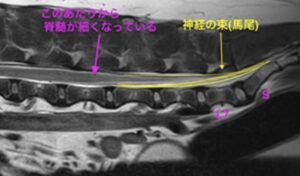

腰から尾のかけての椎間板が背中側へ飛び出しており、上を走っている神経の束を圧迫していた

脊髄は徐々に細くなっていき、そのあたりから神経が束になって尾側に走行している。

この形が馬の尻尾に似ているため、馬尾と呼ばれている。